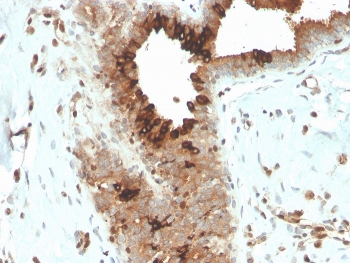

Mammaglobin Antibody - Microarray Specificity Validation (clone MGB/4057R) immunohistochemistry of human breast carcinoma. FFPE human breast carcinoma tissue was stained with Mammaglobin Antibody - Microarray Specificity Validation (clone MGB/4057R). HRP-DAB brown chromogenic signal highlights cytoplasmic staining in tumor epithelial cells lining glandular structures, consistent with expression of Mammaglobin A / SCGB2A2 in breast carcinoma cells, while surrounding stromal cells show little to no staining. Heat-induced epitope retrieval was performed by boiling tissue sections in pH 9 10mM Tris with 1mM EDTA for 20 minutes followed by cooling prior to staining.

IHC staining of FFPE human breast carcinoma with recombinant Mammaglobin antibody (clone MGB/4057R). HIER: boil tissue sections in pH 9 10mM Tris with 1mM EDTA for 20 min and allow to cool before testing.